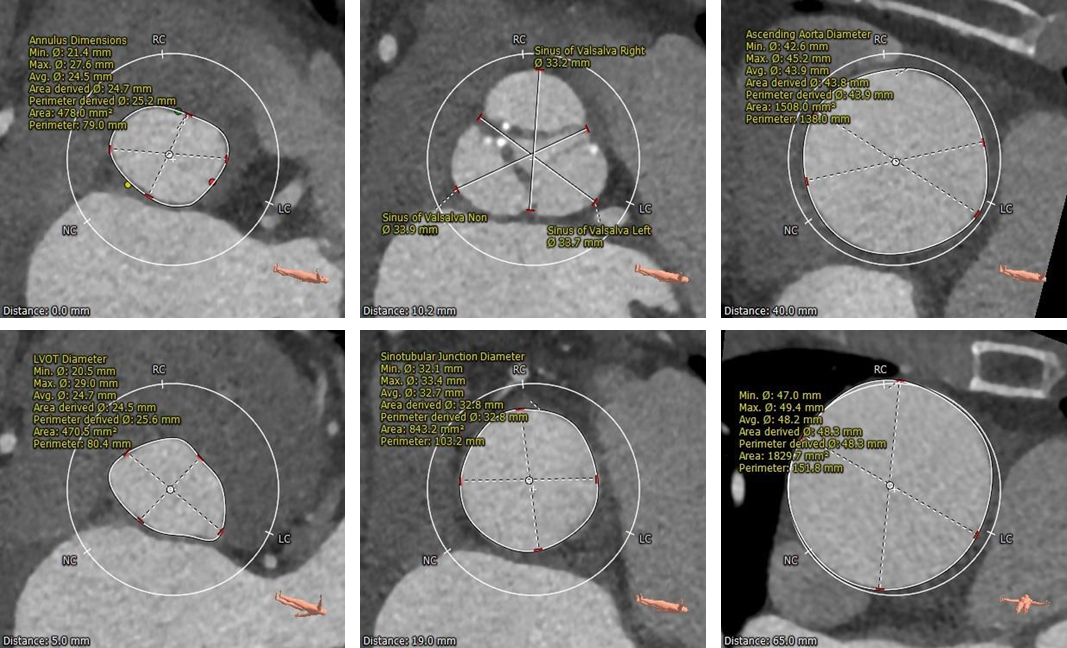

术前CT评估

CT结果显示:

• 三叶式主动脉瓣,瓣叶轻中度钙化,钙化分布欠均匀,主要分布在瓣叶边缘及管壁附着缘,瓣叶严重增厚,局部交接粘连

• 左右冠开口高度尚可,未见明显冗长瓣叶

• 流入端形态呈直桶状,瓦氏窦、窦管交界内径偏大,升主动脉瘤样扩张

• 左室腔内径可,心室壁增厚

• 主动脉瓣环与水平面夹角近70°,横位心,主动脉弓角度与宽度可

• 入路血管散在钙化,双侧血管内径良好,整体入路血管条件良好